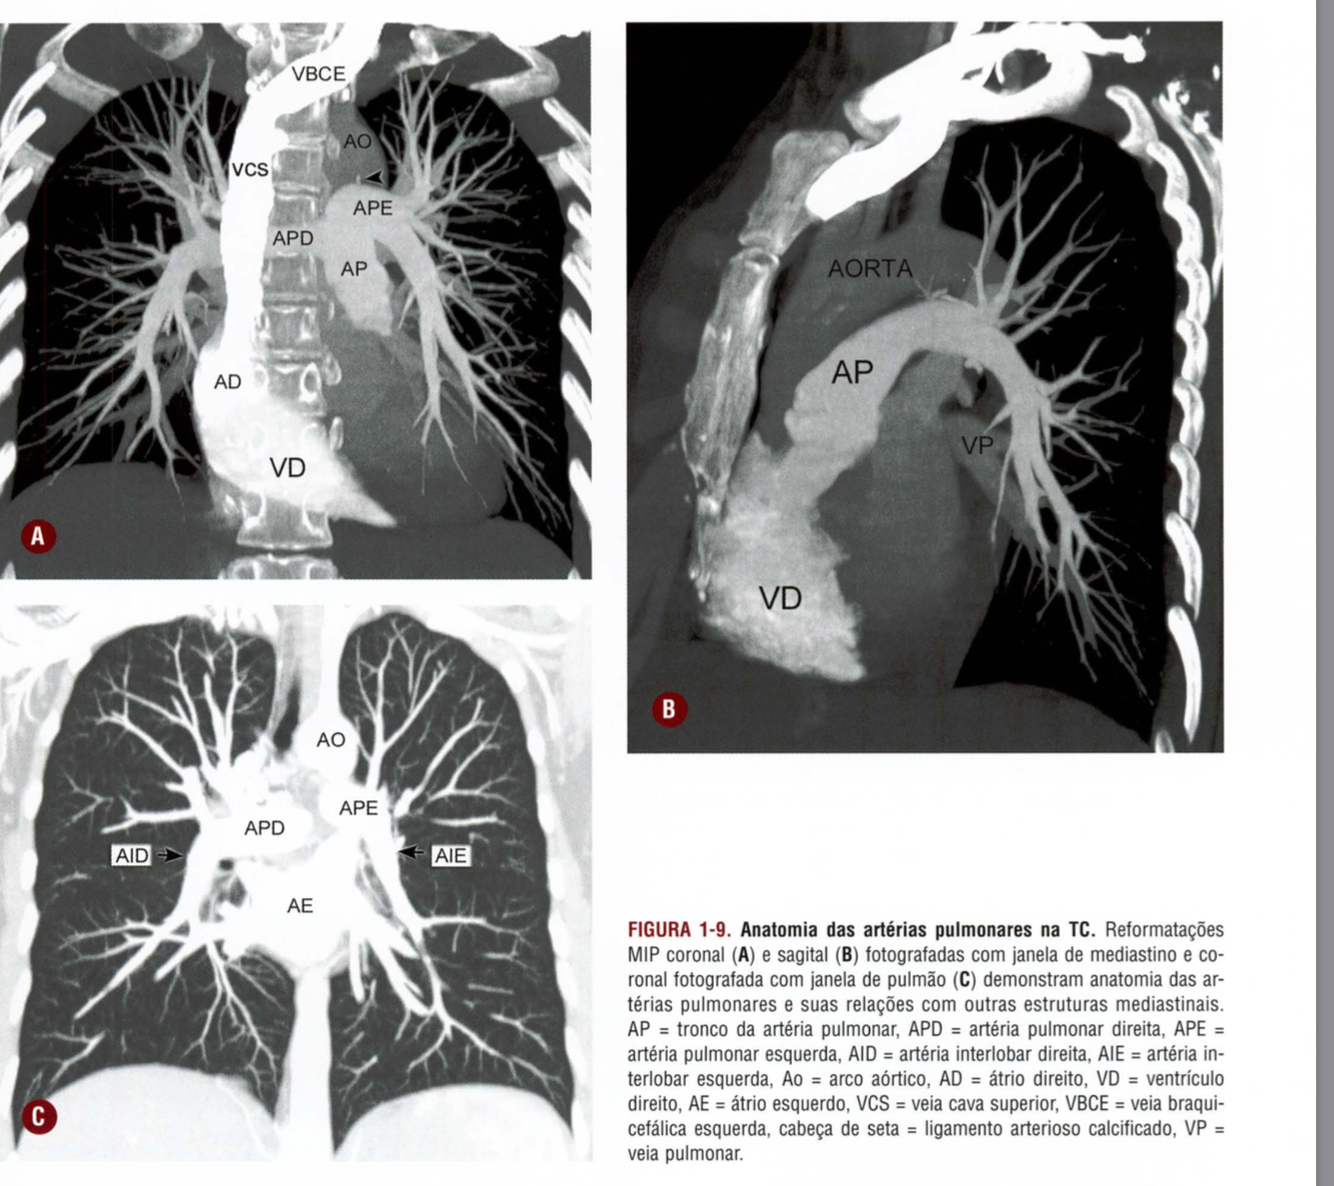

Qual a anatomia vascular básica da janela do mediastino?

Mensuração do diâmetro do tronco da artéria pulmonar

Anatomia das veias pulmonares na TC